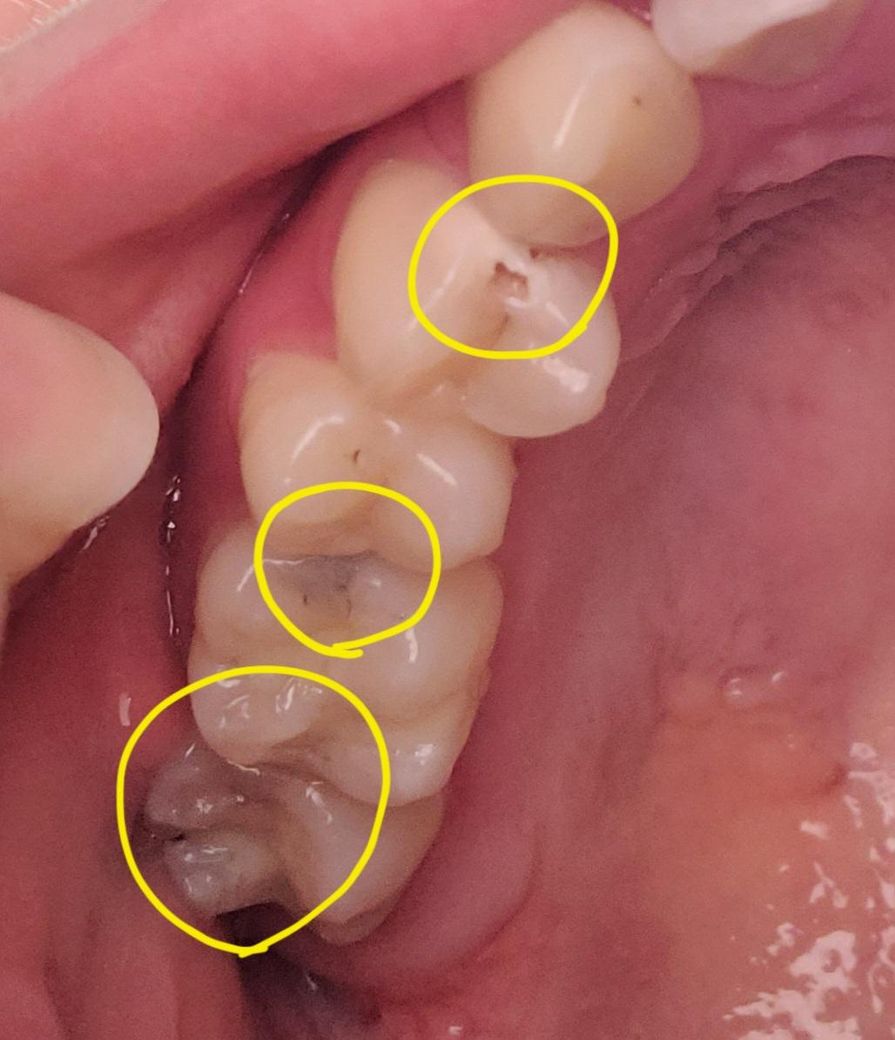

이거 다 충치인가요..? 알려주세요 ㅠ

이것들 다 충치맞나요..?

맨 위에 동그라미는 예전에 레진으로 치료받았던 부분이 맞는지 헷갈려서 그냥 레진이 깨진건지 충치여서 하얗게 썩게 된건지 모르겠어요.. 그리고 나머지 2개는 까맣게 보여서 질문드려요....!

혹시 3개 각각 치료하는데 돈이 얼마나 들까요? 다 레진으로 하는건 불가능하려나요..? 인접면이면 크라운 써야한다는 얘기를 들은 적이 있어서요..ㅠ

말씀하신 모든 부분이 충치로 보여집니다. 일부는 pit & fissure로 점처럼 보여 간단히 레진으로 치료할 수 있으나 충치가 비춰보이거나 충치 부위가 넓다면 인레이나 크라운 등을 해야할 수 있어 보입니다. 인레이나 크라운을 해야하는 경우는 비용이 많이 발생하게 됩니다. 치과 치료 비용은 모두 비급여이므로 치과마다 수가가 다를 수 있습니다. 따라서 정확한 가격을 알기 위해서는 가까운 치과 방문이 필요합니다.

사진으로만 봤을 경우에는 인접면 충치가 있는 것으로 보입니다. 인접면 충치가 있는 경우 충치 부위에 이물질이 끼게 되어 충치가 더 커질 수 있으니 치료를 해주는 것이 좋습니다.

1. 셋다 충치 맞는것으로 판단됩니다

2. 레진으로 한다면 개당 10~15

3. 인레이로 한다면 개당 20~30입니다